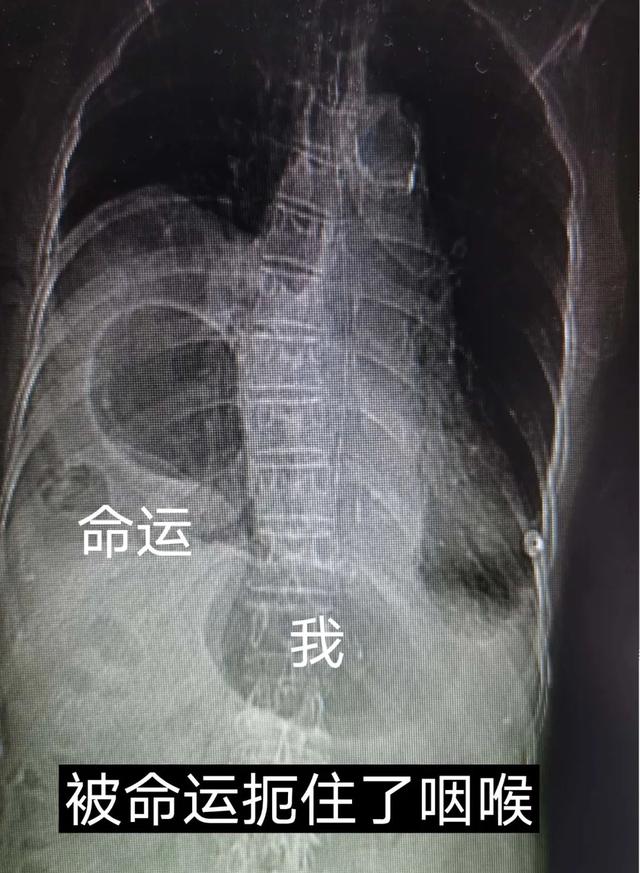

(图为食管裂孔疝,胸腔胃)